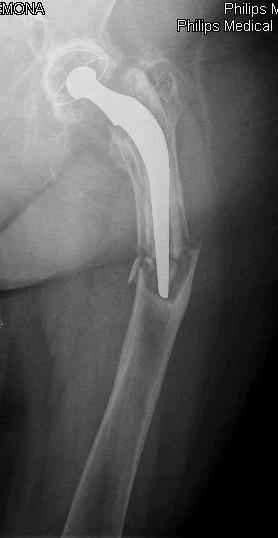

You transformed a cemented hip prosthesis to a cementless revision hip prosthesis with a little approach.

I generally should prefer a long stem revision prosthesis, as that allegated.